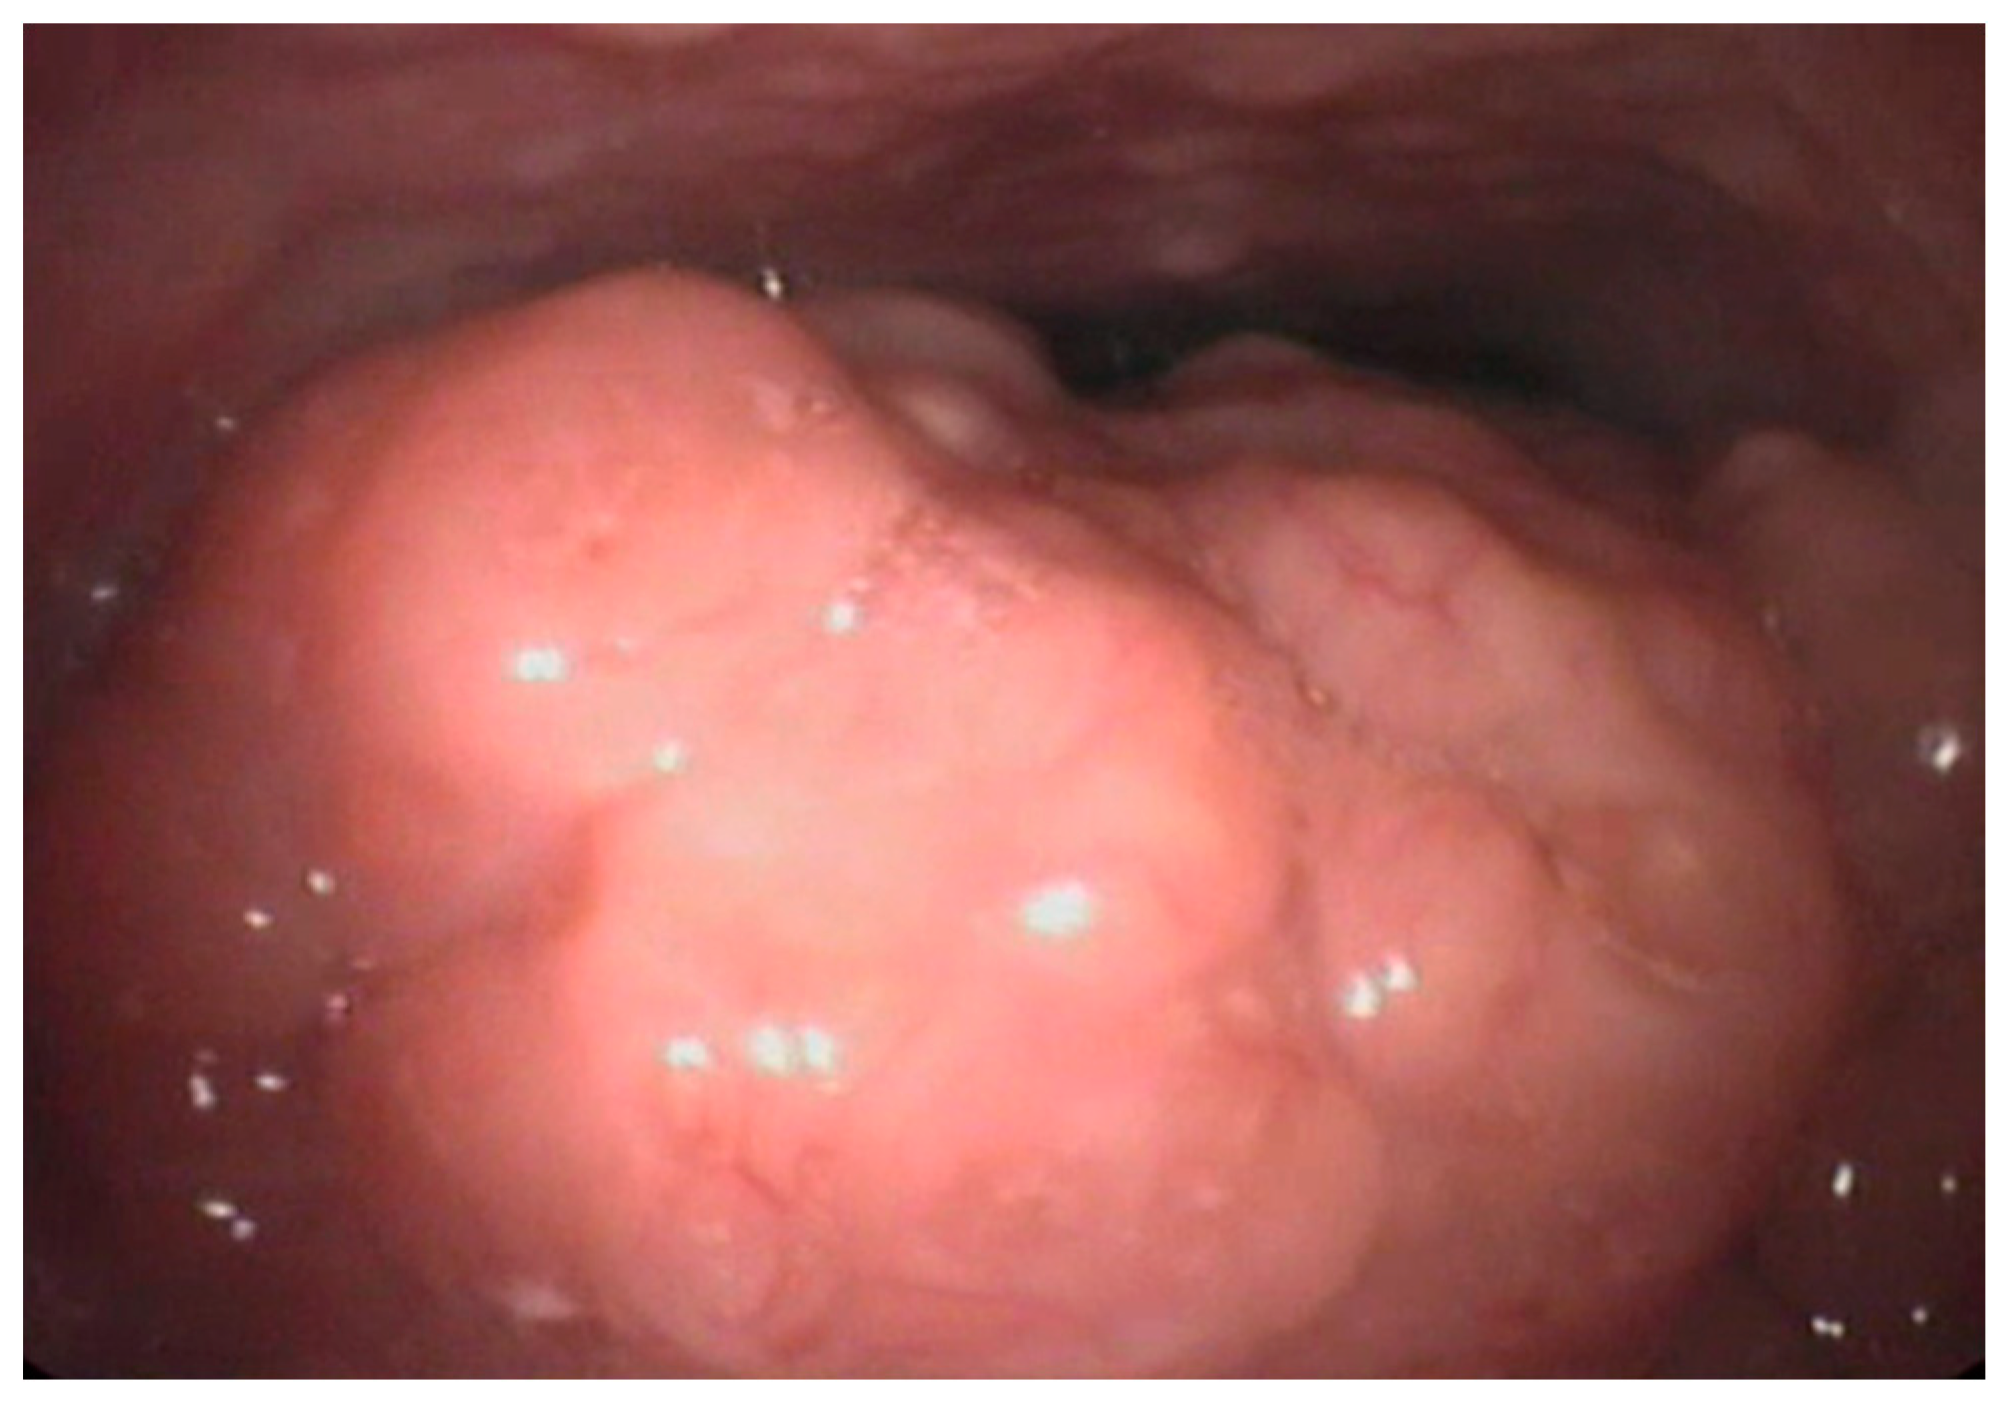

Recent studies have also suggested the role of lingual tonsil hypertrophy in the pathogenesis of pediatric OSAS, as frequent evidenced in the adult population [8,9,10,11,12]. Figure 2 shows lingual hypertrophy in a 11-year-old child. In adults, the procedure of reducing lingual tonsil through Trans Oral Robotic Surgery (TORS) is widely used. In children, it is not a common procedure [38,39]. In particular, the young patient of Figure 3 underwent robotic surgery due to severe OSAS with disabling symptoms without adenotonsillar hypertrophy or other risk factors.

Figure 2.

Lingual tonsil hypertrophy in a 11 year-old child. Courtesy of Professor C. Vicini—Department of Head-Neck Surgery, Otolaryngology, Head-Neck and Oral Surgery Unit, Morgagni Pierantoni Hospital, Forlì, Italy.